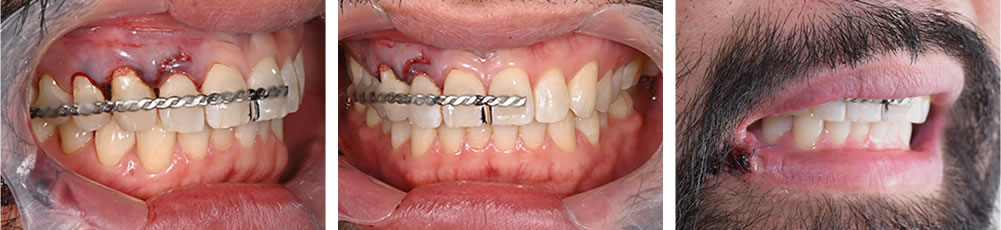

歯の固定

歯を正しい位置に戻した後、ワイヤーにて固定を行いました。

根管治療の実施

歯の固定から2週後に根管治療を開始し、MTAセメントにて精密な根管充填を行いました。根管充填後はコンポジットレジンにて歯冠修復を行いました。